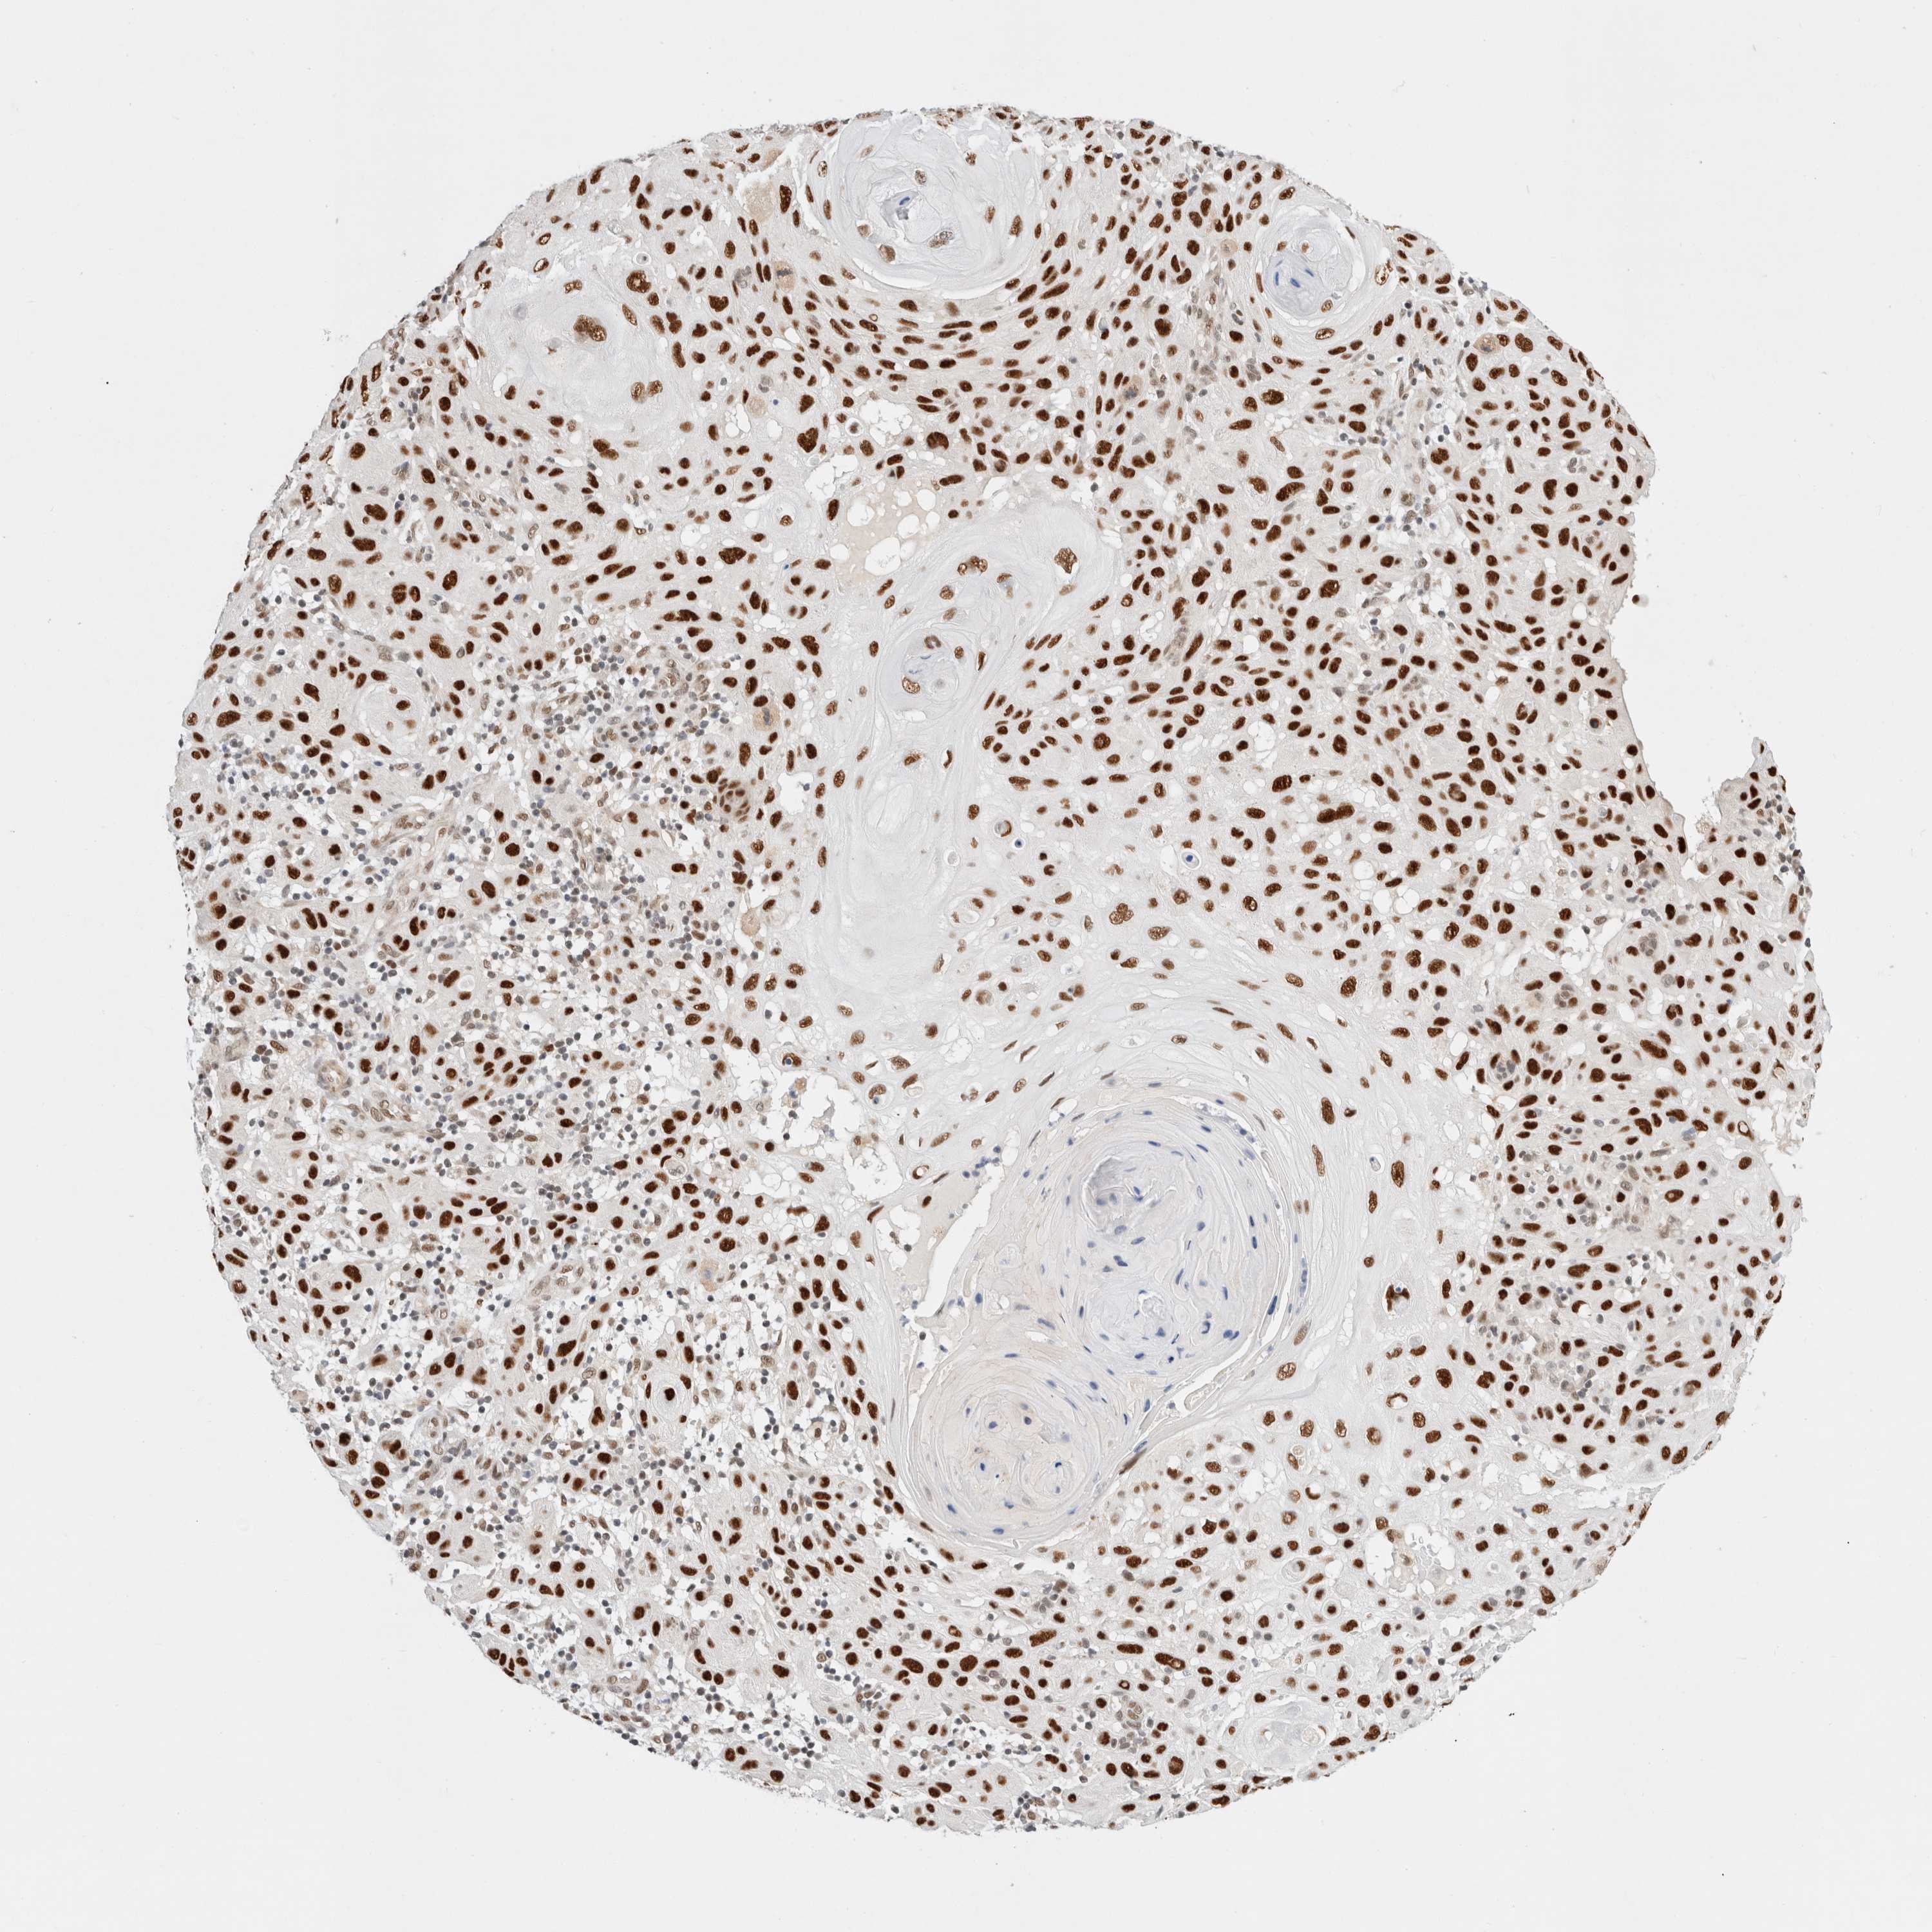

SKIN CANCER - Protein expressioni

A mouse-over function shows sample information and annotation data. Click on an image to view it in a full screen mode. Samples can be filtered based on level of antibody staining by selecting one or several of the following categories: high, medium, low and not detected. The assay and annotation is described here.

Antibody stainingi

Antibody staining in the annotated cell types in the current human tissue is reported as not detected, low, medium, or high, based on conventional immunohistochemistry profiling in selected tissues. This score is based on the combination of the staining intensity and fraction of stained cells.

Each image is clickable and will lead to virtual microscopy that enables deeper exploration of all samples and also displays staining intensity scores, fraction scores and subcellular localization as well as patient and tissue information for each sample.

Antibody HPA026638

Antibody CAB004595

Basal cell carcinoma

Squamous cell carcinoma, NOS

Squamous cell carcinoma, metastatic, NOS